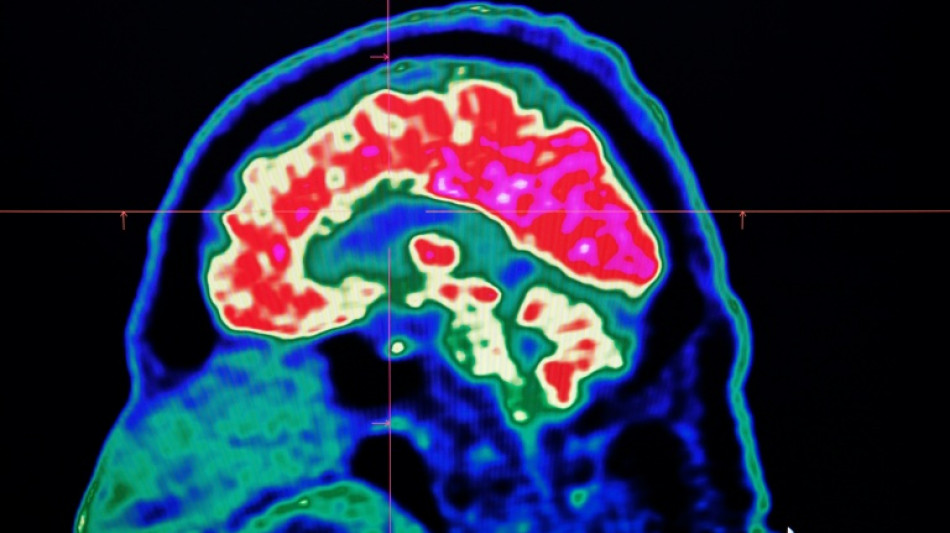

Final report casts doubt on existence of Canada mystery brain illness

A Canadian medical report published Friday found no evidence linking environmental factors to an unusual set of neurological symptoms affecting hundreds of people, a five-year saga that has shaken a small Atlantic province.

In 2021, health officials in New Brunswick launched an investigation involving 48 patients with a range of neurological symptoms but no apparent common illness. These included muscle spasms, memory loss, hallucinations and balance issues.

Some in the province of less than a million people began describing the condition as a mystery brain disease.

Provincial officials said at the time that the patient group could be suffering from a new disease not previously seen in Canada and began using the term "possible neurological syndrome of unknown cause."